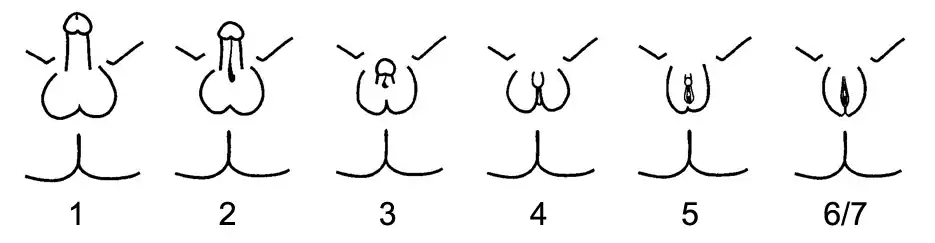

A supplemental system of phenotypic grading that uses seven classes instead of the traditional three was proposed by pediatric endocrinologist Charmian A. Quigley et al. in 1995.[3] The first six grades of the scale, grades 1 through 6, are differentiated by the degree of genital masculinization; grade 1 is indicated when the external genitalia is fully masculinized, grade 6 is indicated when the external genitalia is fully feminized, and grades 2 through 5 quantify four degrees of increasingly feminized genitalia that lie in the interim.[3] Grade 7 is indistinguishable from grade 6 until puberty, and is thereafter differentiated by the presence of secondary terminal hair; grade 6 is indicated when secondary terminal hair is present, whereas grade 7 is indicated when it is absent.[3] The Quigley scale can be used in conjunction with the traditional three classes of AIS to provide additional information regarding the degree of genital masculinization, and is particularly useful when the diagnosis is PAIS.[2][16]

Given the wide diversity of phenotypes associated with PAIS, the diagnosis is often further specified by assessing genital masculinization.[2][3] Grades 2 through 5 of the Quigley scale quantify four degrees of increasingly feminized genitalia that correspond to PAIS.[3]

Grade 2, the mildest form of PAIS, presents with a predominantly male phenotype that presents with minor signs of undermasculinized genitalia, such as isolated hypospadias,[3] which can be severe.[1] Hypospadias may manifest with a partially formed channel from the urethral opening to the glans.[3][36] Until recently, it was thought that isolated micropenis was not a manifestation of PAIS.[1] However, in 2010, two cases of PAIS manifesting with isolated micropenis were documented.[37]

Grade 3, the most common phenotypic form of PAIS,[1][31] features a predominantly male phenotype that is more severely undermasculinized, and typically presents with micropenis and pseudovaginal perineoscrotal hypospadias with bifid scrotum.[3]

Grade 4 presents with a gender ambiguous phenotype, including a phallic structure that is intermediate between a clitoris and a penis.[3] The urethra typically opens into a common channel with the vagina (i.e. urogenital sinus).[3]

Grade 5, the form of PAIS with the greatest degree of androgen insensitivity, presents with a mostly female phenotype, including separate urethral and vaginal orifices, but also shows signs of slight masculinization including mild clitoromegaly and / or partial labial fusion.[1][3]